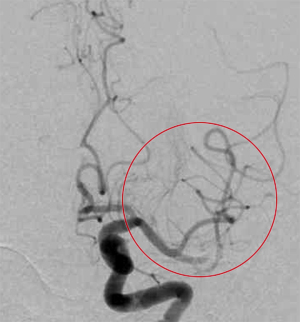

動脈瘤

動脈瘤については未破裂脳動脈瘤では治療がよいか、経過観察でもよいかを検討します。一方破裂した人(突発的な頭痛と吐き気の出現)は、クモ膜下出血となり再出血しやすいので緊急の治療を要します。破裂、未破裂にかかわらず治療に際しては、個人の状態により開頭クリッピング術とカテーテルを用いたコイル塞栓術のいずれか適切な方を選択しています。

これまで治療の難しかった内頚動脈の動脈瘤に、フローダイバイターを用いた最新のステント治療を行っています。

開頭クリッピングの手術前

開頭クリッピングの手術後

コイル塞栓手術前

コイル塞栓手術後